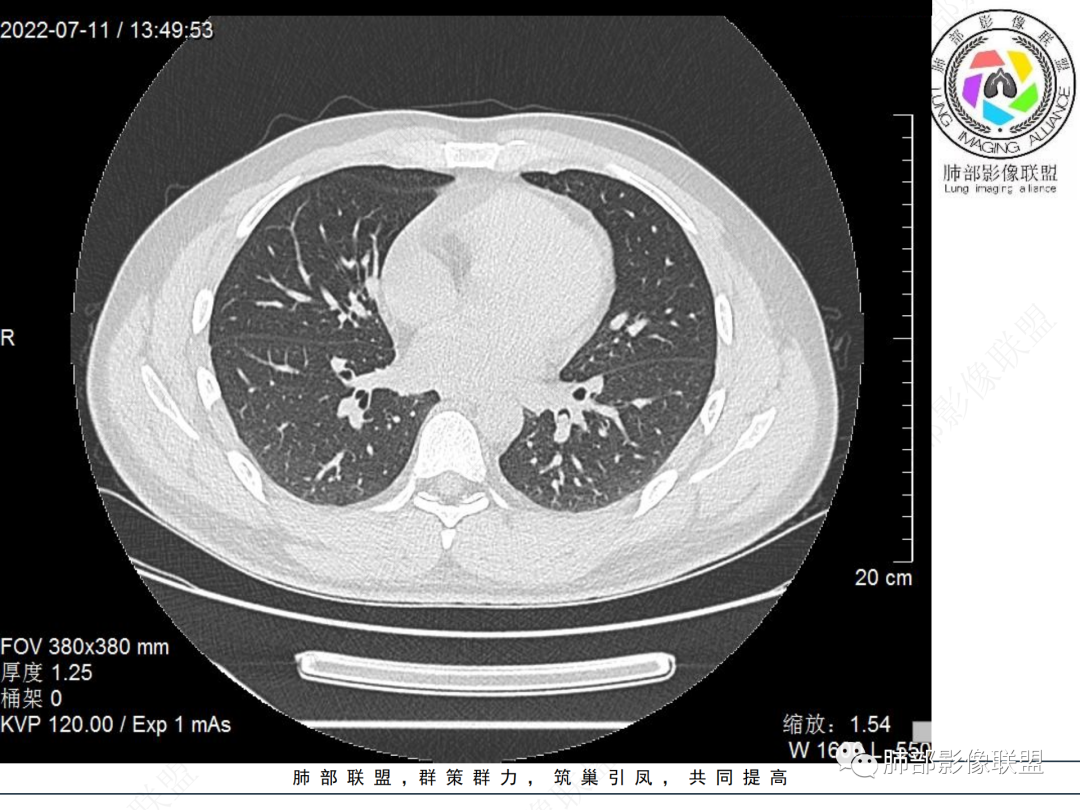

左肺下叶后基底段开口处结节,边缘光滑清楚,没有增强扫描,年轻男性患者痰血三天,考虑1.良性病变:腺瘤、错构瘤、平滑肌瘤

2.恶性:类癌、粘液表皮样癌。

左肺下叶外后基底段气管内见结节状影,边缘部分清晰。考虑错构瘤,待排恶性病变。

左肺下叶气管内外占位病变,咯血病史,考虑类癌,粘表待排。

青年男性,左肺下叶后基底段支气管开口软组织结节,边缘光整,气管镜提示质软,易出血,考虑类癌

左肺下叶后基底段开口处结节,边缘光滑清楚,年轻患者考虑鳞癌或腺样囊腺癌

左肺下叶气道腔内占位,远端无花花草草,疾病谱:鳞,类癌,粘表,腺样囊腺癌,小,无增强,不好判断,临床咯血,选类癌。

大支气管腔内结节,考虑类癌

左肺下叶后基底段开口处结节影,边缘光滑,患者年龄较小,首选类癌

男性,咳血左肺下叶支气管腔内结节影,没有阻塞性炎症,考虑类癌,鳞癌

年轻男性,支气管内结节,首先类癌

左肺下叶后基底段开口处腔内见壁结节,花生米样,宽基底,补充增强及矢状位重建,确定我无向壁外突破浸润生长,另见强化的特点,临床触之易出血,类Ca可能性大。

年轻男性,支气管腔内占位,边缘尚平整,年轻人,首先类癌,鉴别错构

年轻男性,咳血,左肺下叶后基底段支气管腔内结节,边缘光滑,首先考虑青年三件套,类癌大于粘液表皮样癌,支气管镜质软,触之易出血,鉴别血管瘤,平滑肌瘤

左肺下叶后基底段开口部结节,密度较均匀一致,边缘较光整,目测密度偏低,支气管镜示:质软、触之易出血,考虑恶性,类癌。

支气管腔内结节,有蒂与支气管壁连接,考虑良性病变可能性大,支气管错构瘤  血管瘤一类的

左肺下叶后基底段支气管腔内结节,有蒂,容易出血,先考虑良性病变,肉芽组织型血管瘤,与类癌鉴别。

青年男性,左肺下叶后基底段支气管开口软组织结节,边缘光整,气管镜提示质软,易出血,考虑恶性类癌

左肺下叶后基底段开口处结节影,边缘光整,年轻患者,伴咯血,考虑鳞癌,类癌不能排除